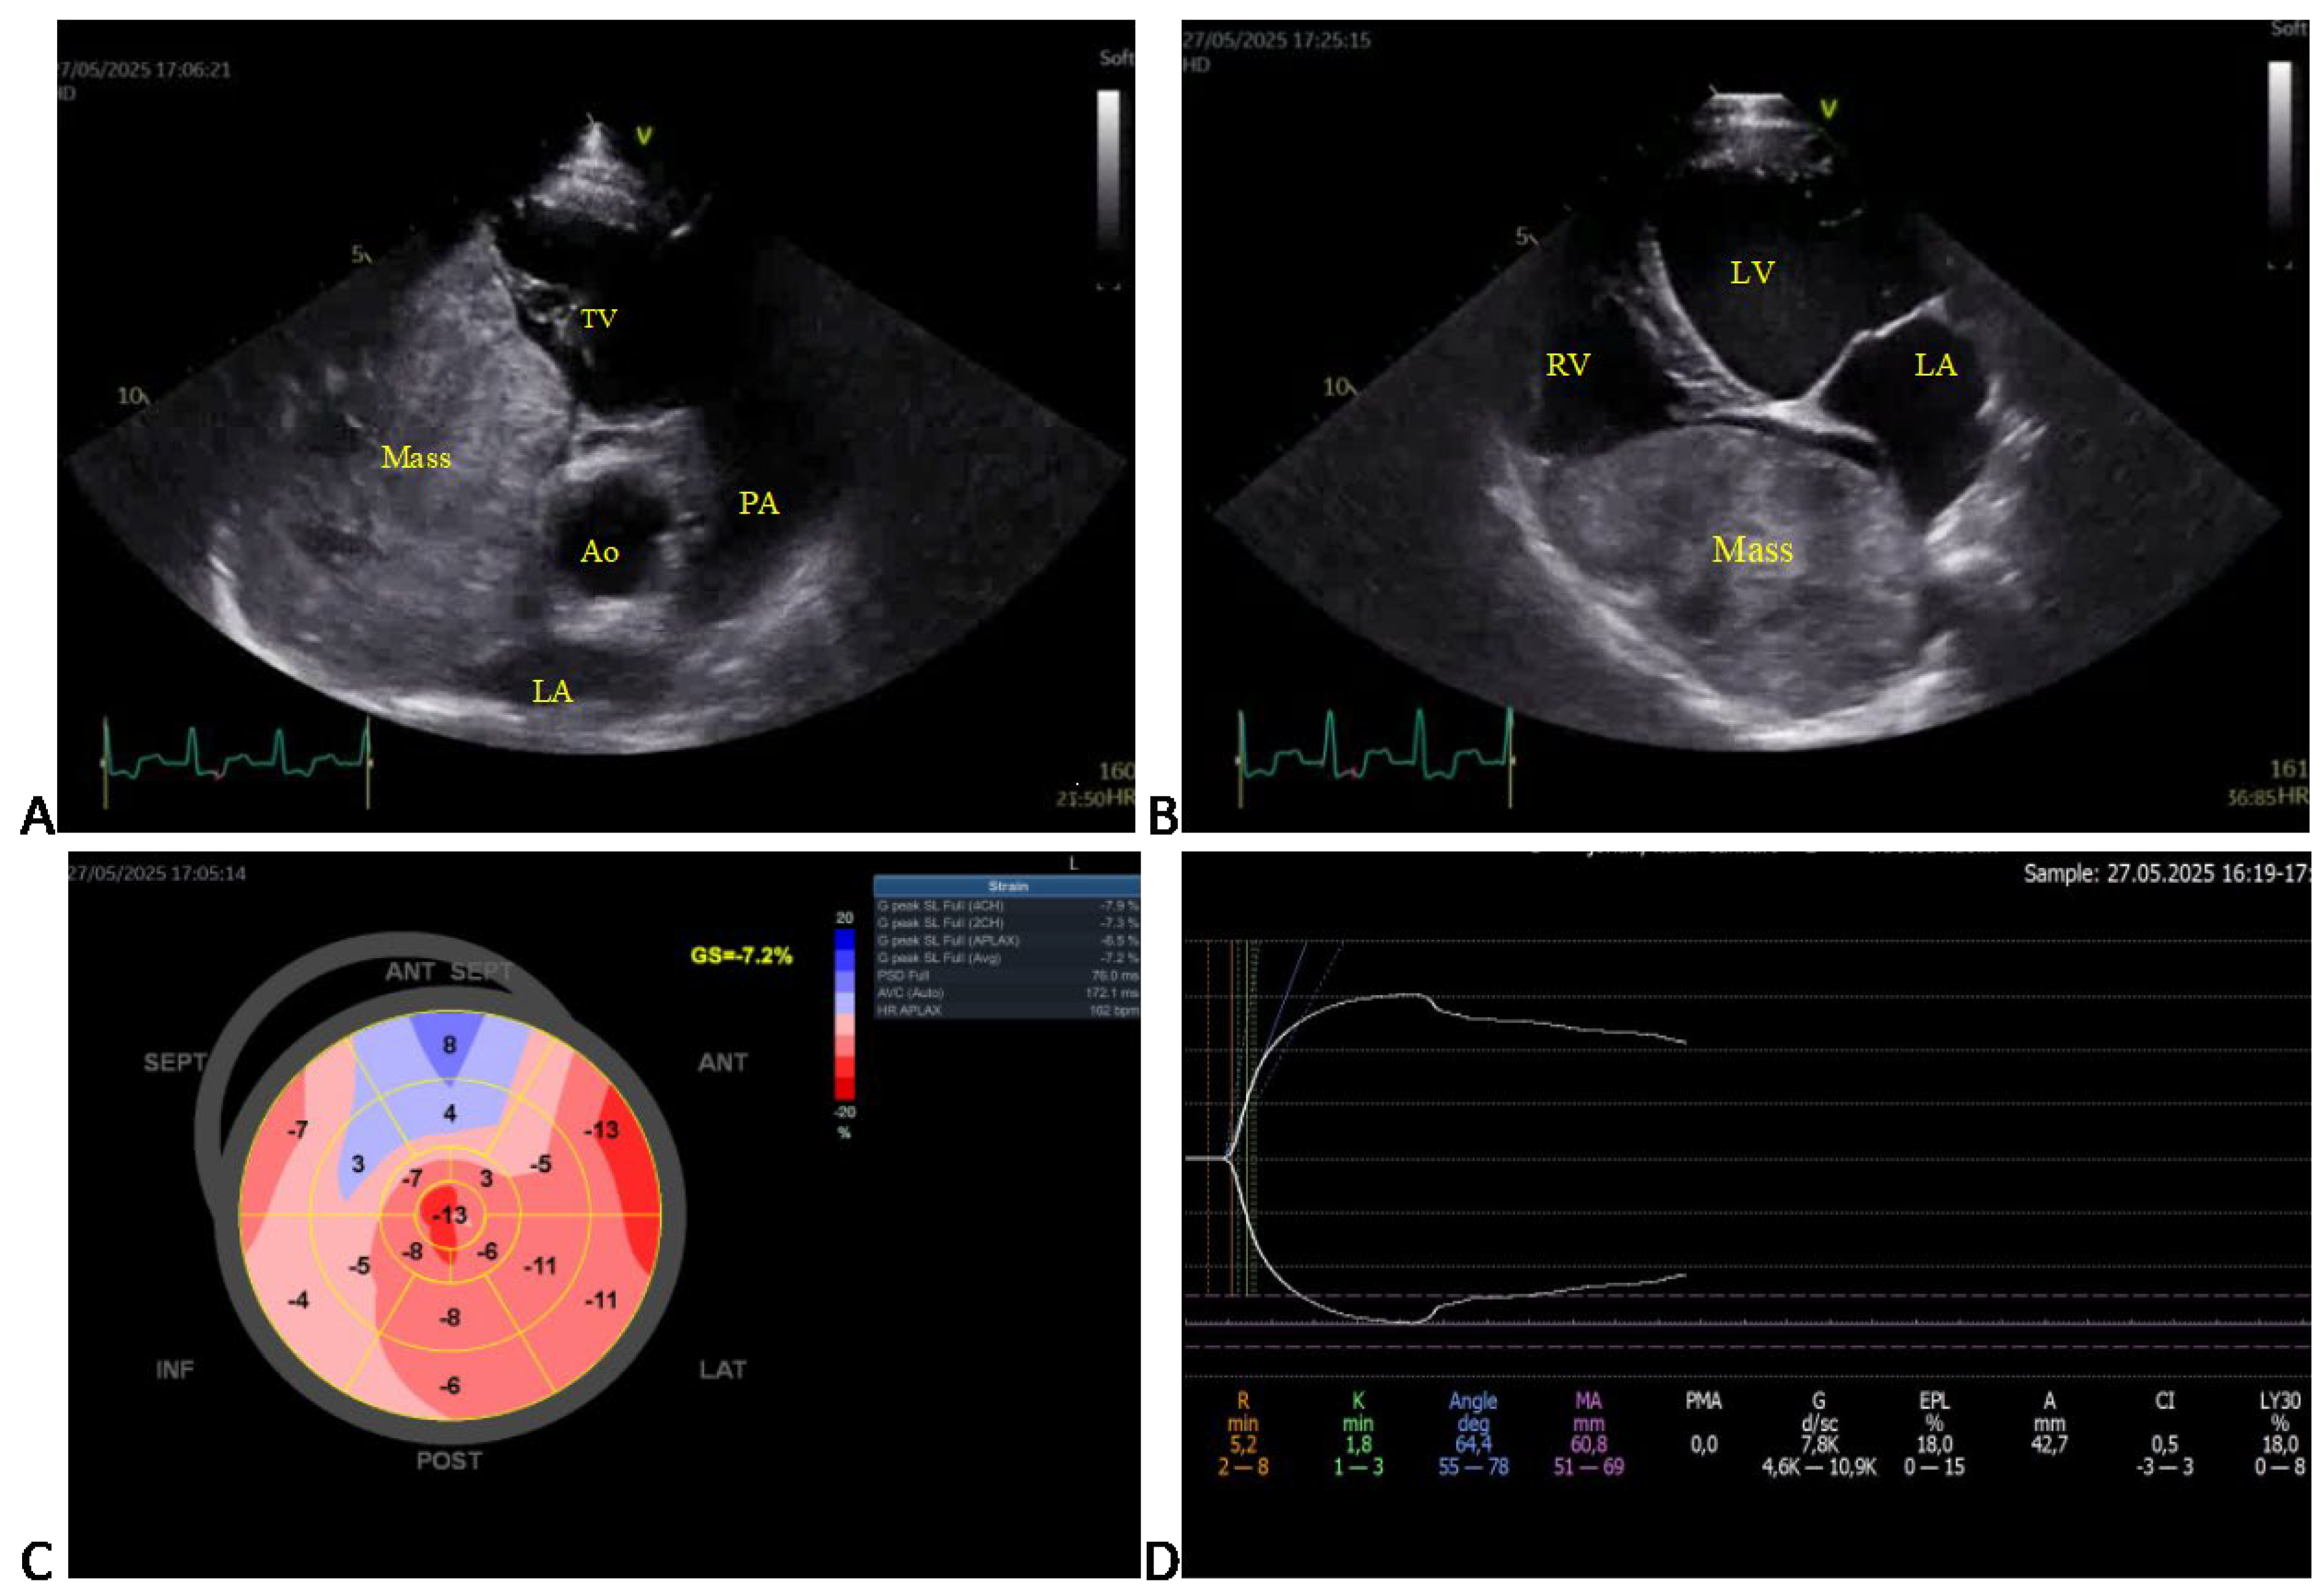

3.3. Echocardiographic Findings

3.4. Diagnostic Imaging and Cytological Findings